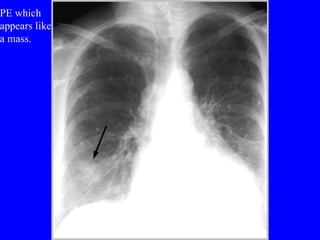

Pulmonary embolism (PE) is a common and potentially fatal condition where blood clots block arteries in the lungs. An estimated 5 million venous thromboses occur annually worldwide, with 10-30% of PE cases correctly diagnosed. Risk factors include older age, cancer, obesity, surgery, trauma, and genetic or acquired hypercoagulable states. Diagnosis involves assessing clinical probability based on symptoms and risk factors, then confirming with tests like D-dimer, chest imaging, ventilation-perfusion scanning, pulmonary angiography, or CT pulmonary angiography. Treatment focuses on anticoagulation to prevent further clotting while allowing natural lysis of existing thrombi.